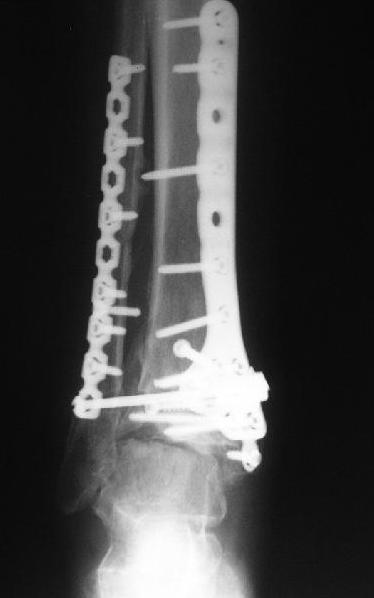

Dear коллеги,Обратилась женщина, 25 л. 8 мес. назад в одной из больниц сделан остеосинтез пилона. На сегодня ходит без дополнительной опоры, хромая на поврежденную ногу. Движения в голеностопном суставе еще есть. Снимки в приложении.

A female, 25, 8 month ago operated elsewhere. To date walks without support with pain and limp. The ankle is mobile yet. Images attached.The question is what to do now? The patient is not very keen on ankle fusion (though likely could change her mind if necessary)Is it worth to try a reconstruction procedure and what kind? Maybe it allows to restore alignment and tibio-fibular relationship - will it provide painless limb for more or less significant time?Or just remove the hardware and leave her alone until she herself comes for fusion?

CT images/xrays confirm incongruity of articular surfaces as well as intraarticular screws.

Александр, добрый вечер! К сожалению, боюсь, что, кроме артродеза, ничего не осталось, упущено время. Просто убрать железо конечно можно, а куда деть вальгусную установку, "синдесмоз", признаки артрофиброза, которые прослеживаются на представленных рентгенограммах. Вопрос же стоит в качестве жизни пациентки, может ей тактично все объяснить, что чем дольше она будет так ходить, тем возможно болевой синдром будет более стойким и усилится деформация.

Коллега.сли говорить о возможных операциях, то лучкий вариант это артродез голеностопного сустава. Учитывая выраженные изменения со строны сустава, неустранённую вальгусную деформацию, артропластика и эндопротезирование дискутабельно.